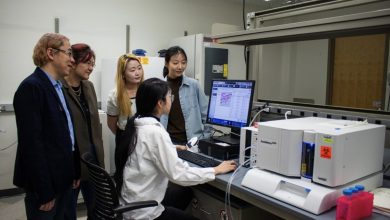

Pesquisadores desenvolvem uma nova maneira de aumentar com segurança as células imunológicas para combater o câncer

(Em pé, a partir da esquerda) Rong Tong, professor associado de engenharia química; Wenjun “Rebecca” Cai, professor associado em ciência…